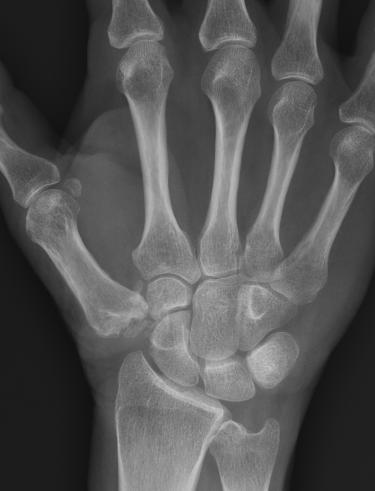

Eaton Classification

| Stage I | Stage II | Stage III | Stage IV |

|---|---|---|---|

|

Xray normal Synovitis |

Joint space narrowed Mild subluxation |

Severe joint space OA Radial subluxation of joint |

CMC + STT OA |

![]() |